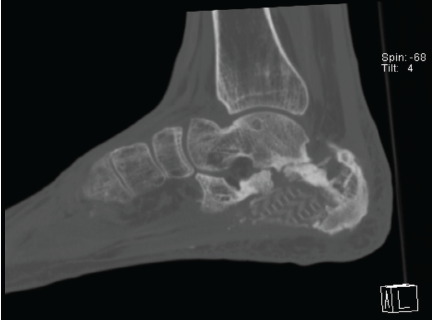

Post-operative Microdiscectomy Complicated by Lumbar Epidural Hematoma with Cauda equina Syndrome Following Dual Viral Infection: A Rare Case Report and Its Management